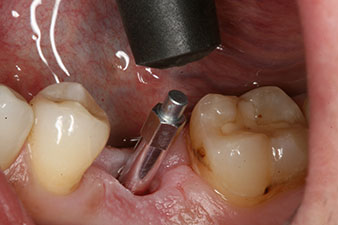

Fig. 3: After preparation with the Implantmed implantology motor, an implant (diameter 4 mm, length 12 mm) was screwed in by the motor at a torque of 43 Ncm.

The implant was placed as planned after thorough removal of the granulation tissue (blueSky, bredent).

SmartPeg

Fig. 4: SmartPeg measuring posts screwed on to measure the implant stability quotients with the integrated W&H Osstell ISQ module.

The torque used for the machine-driven placement was 43 Ncm. In addition, after screwing a measuring post (SmartPeg) specially matched to the implant, the ISQ value was measured with the probe of the W&H Osstell ISQ module.